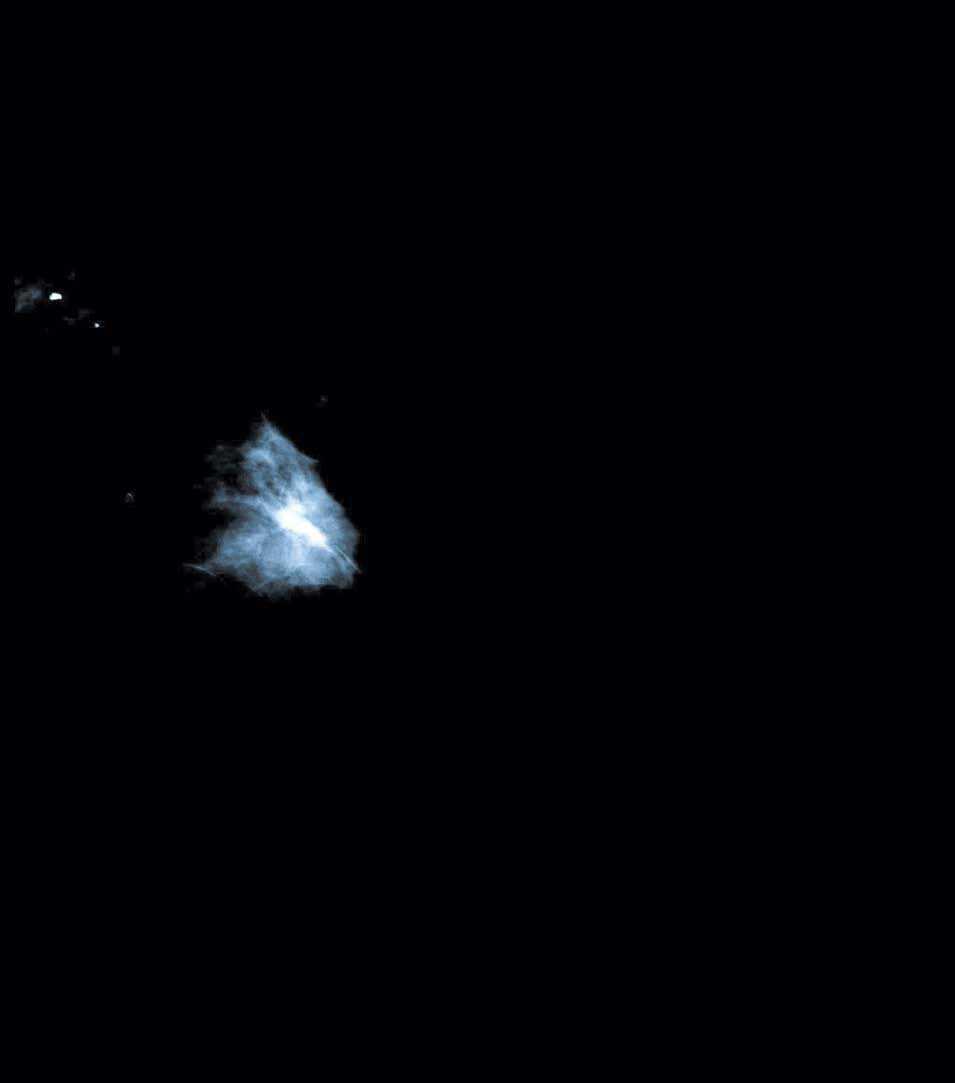

En una mamografía de control, realizada en marzo de 2004, se visualizó en los intercuadrantes superiores de la mama izquierda, hacia el cuadrante superoexterno, una lesión nodular con bordes espiculados y alguna probable microcalcificación en el interior (figs. 1 y 2). En la ecografía se confirma la presencia de una lesión sólida, hipoecogénica, que no produce amortiguación del sonido, compatible con un proceso neoformativo; en la axila se distingue una adenopatía de 1,3-2,3 cm, de aspecto inflamatorio residual.

Figura 1. Mamografía izquierda. Lesión nodular.

Figura 2. Mamografía izquierda. Lesión nodular.